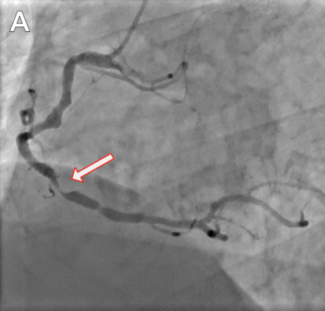

A 78-year-old woman with a history of hypertension, hyperlipidemia, and asthma was referred to her cardiologist for chest pain and dyspnea on exertion. An electrocardiogram showed biphasic T waves in precordial leads (V1-3). Left and right...